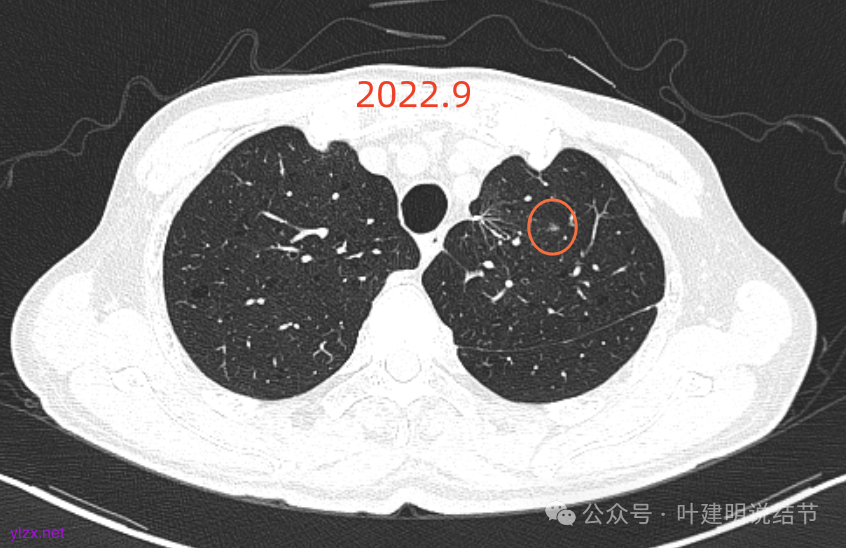

再看2022年9月的:

右上病灶此层面偏长条,密度较低。

左上已经手术。

左上另有一处磨玻璃结节,由于手术后结构变化,此灶是术前哪处感觉不太好对比。